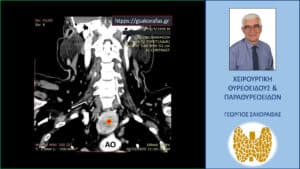

Γιγάντια καταδυόμενη βρογχοκήλη σε ασθενή με «δύσκολο» τράχηλο και βαθιά κατάδυση (μέχρι το αορτικό τόξο) – διατραχηλική εκτομή (χωρίς στερνοτομή) με ταυτόχρονη παραθυρεοειδεκτομή για τυχαία διαγνωσθέν αδένωμα παραθυρεοειδούς. Αξονική τομογραφία – εικόνα σε κατά μέτωπο διατομή: Ο καταδυόμενος αριστερός λοβός (κόκκινος αστερίσκος) εκτείνεται σε βάθος στο μεσοθωράκιο φθάνοντας στο άνω όριο του αορτικού τόξου (ΑΟ) μεταξύ της έκφυσης της ανωνύμου αρτηρίας (κόκκινο βέλος) και της αριστεράς κοινής καρωτίδας (πράσινο βέλος).